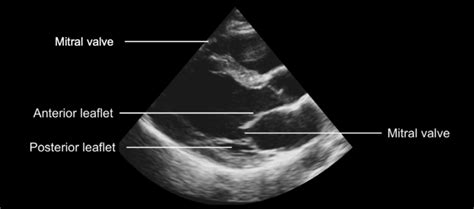

Guys, let’s talk about the unsung hero in detecting that hockey stick mitral valve echo : echocardiography . This imaging technique is absolutely critical, and honestly, it’s the gold standard for visualizing this specific abnormality. Echocardiography, or ‘echo’ as we commonly call it, uses high-frequency sound waves to create real-time images of your heart. Think of it like sonar for your heart! A technician, usually called a sonographer, places a transducer (a wand-like device) on your chest, and these sound waves bounce off the different structures of your heart – the chambers, the walls, and of course, the valves. The echoes are then processed by a computer to build detailed pictures and even moving images of your heart in action. For detecting the hockey stick mitral valve echo , echocardiography is invaluable because it allows us to see the dynamic motion of the mitral valve leaflets throughout the cardiac cycle. We’re not just looking at a static picture; we’re watching how the anterior mitral valve leaflet moves as the heart beats. In a healthy heart, this leaflet opens widely and gracefully during diastole to allow blood flow. However, in conditions like hypertrophic cardiomyopathy (HCM), the thickened septum pushes into the ventricular cavity. The echocardiogram clearly shows how this abnormal anatomy affects the leaflet’s movement. We can visually track the anterior leaflet being drawn towards the thickened septum, creating that characteristic elongated, curved, ‘hockey stick’ shape. Different views within the echocardiogram, like the parasternal long-axis view, are particularly useful for observing this phenomenon. Doppler ultrasound, another component of echocardiography, can also assess blood flow patterns. It can help quantify the degree of left ventricular outflow tract (LVOT) obstruction that often accompanies the hockey stick mitral valve appearance. This helps the doctor understand the severity of the condition and its impact on blood flow. The diagnostic power of echo is immense. It can differentiate between various causes of heart conditions, assess the extent of muscle thickening, measure chamber sizes, and evaluate overall heart function. When it comes to the hockey stick mitral valve echo , it’s a very specific sign that guides the clinician towards a diagnosis of HCM or similar obstructive conditions. Without echocardiography, identifying this subtle yet significant dynamic abnormality would be incredibly difficult, if not impossible. It’s a non-invasive, readily available, and highly informative tool that provides a window into the intricate mechanics of the heart, allowing for precise diagnosis and effective management planning. So, next time you hear about an echo, remember it’s a sophisticated piece of technology doing some truly amazing work, especially when it comes to spotting signs like the hockey stick mitral valve.